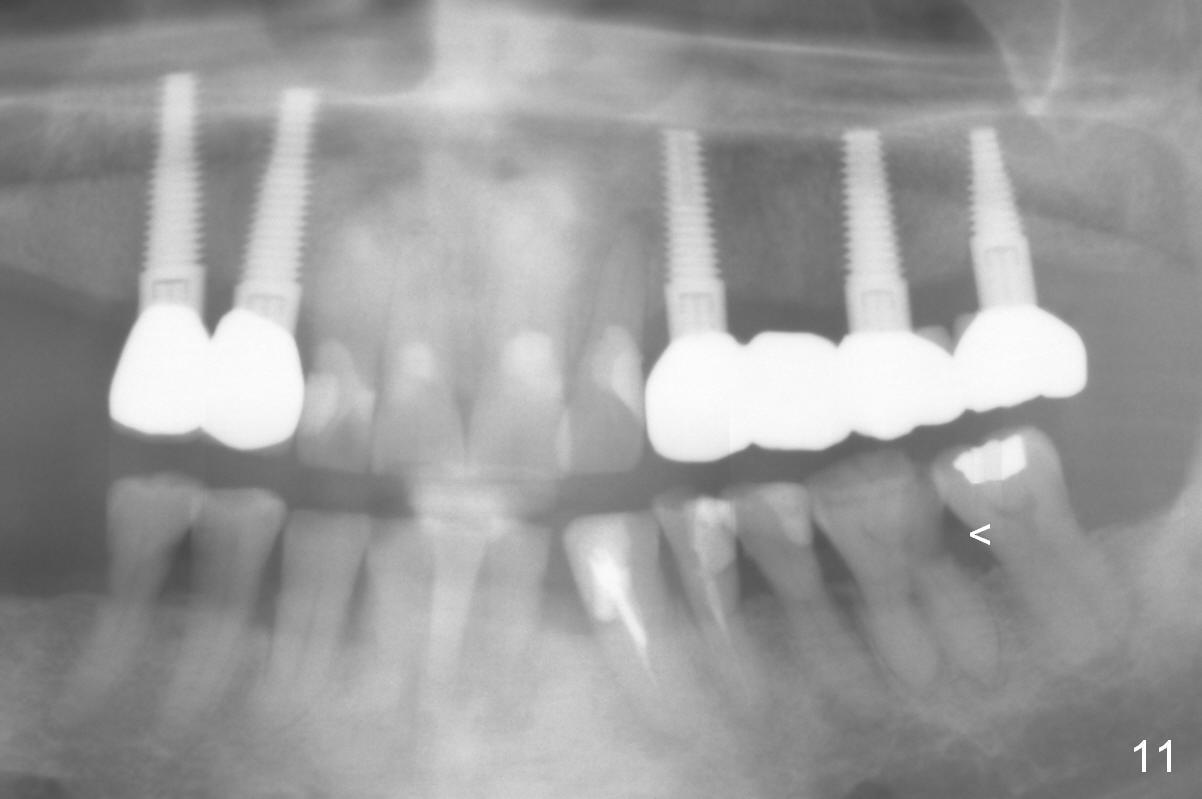

Maxillary Buccal Plate Fracture Due to Bone Expansion

The edentulous ridge distal to #11 residual root is moderately atrophic (Fig.1). The ridge is split with 10 and 13 mm saws between initial osteotomies at #12,14 and 15 (Fig.2). Parallel pins are inserted for trajectory confirmation (Fig.3,4). The gap of the split ridge between #12 and 14 increases when bone expanders (2.7/3.6 mm) are being inserted. A 4.5x17 mm implant does not obtain primary stability at #12. When a 5x17 mm implant is being placed at #12, the buccal plate starts to crack. When the same implant is placed at #14, the crack appears to get larger. Drills are used to finish osteotomy at #14 with force being applied palatally. When the implant is re-inserted, the buccal plate fractures does not appears to get worse (Fig.5 <). In contrast, there is no obvious increase in the gap between #14 and 15 when bone expanders are being used at #15. To avoid complication, drills are used to finish osteotomy before placing a 4.5x14 mm at #15 (Fig.7 (#11: 4.5x17 mm)). CBCT shows that the bone density at #12 and 14 (400-500 Hounsfield units (HU)) is higher than that at #15 (200-300 HU). Ridge split is successful when HU is <200 with smaller diameter implants.

The patient keeps complaining of mastication pain on the left, 4 months post cementation (Fig.11). In fact, there is distal caries at #19 (<).